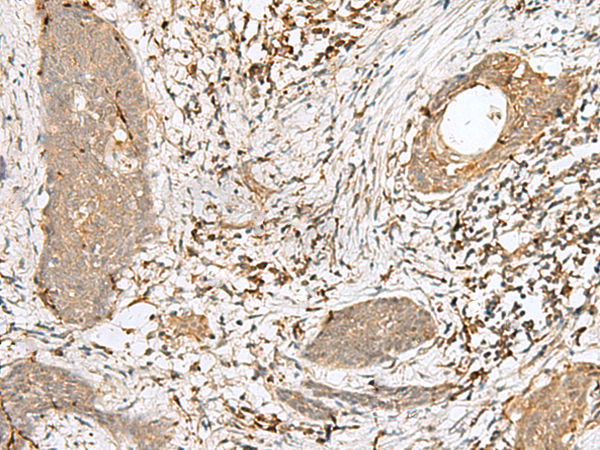

分类: 科研抗体货号: P09846别名: MTQ2; HEMK2; N6AMT; PRED28; C21orf127; m.HsaHemK2P应用: IHC反应种属: Human